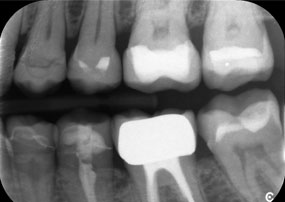

A x-ray, showing teeth and a zirconia crown, in front of a black background.

Figure 2: Replacement of a damaged zirconia crown: Precise removal and renewal of a damaged zirconia crown on tooth 6 with minimal material loss.

A second case highlighting the clinical capabilities of the Power Edition involved the replacement of a damaged zirconia crown in a 63-year-old patient. The patient presented with a chipped veneer on her 20-year-old zirconia crown on tooth 6. Despite the posterior location, the patient found the defect bothersome and requested a new restoration.

The Power Edition enabled precise sectioning, with the increased torque and enhanced cooling contributing to the controlled removal of the crown without significant material loss. The chucking system and enhanced torque proved to be essential in this process.